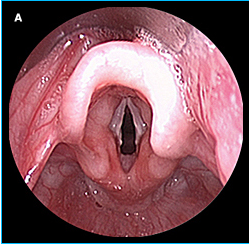

Epiglotis

Epiglotis